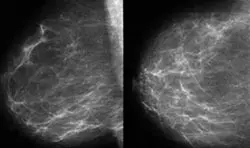

Meme Radyolojisi

Dijital mamografi nedir ?

Digital mamografinin avantajları var mıdır?